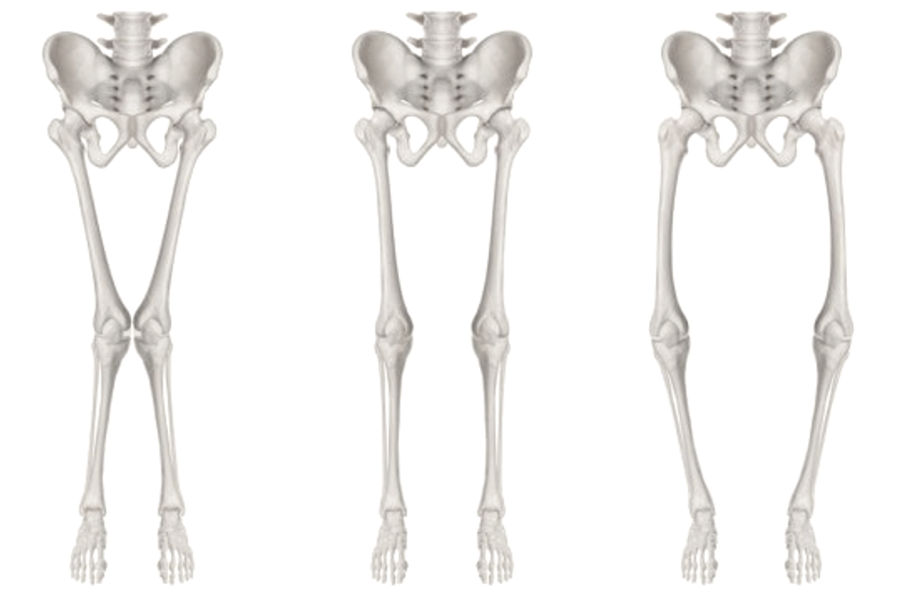

Son yıllarda, diz protezi sonuçlarını daha da iyileştirmek için yapılan çalışmalardan bir tanesi de kişiye özel dizilim felsefelerinin uygulanmaya başlanmış olmasıdır. Yapılan araştırmalar, bu yöntemle yapılan diz protezlerinin sonuçlarının daha iyi olduğu, hastaların ameliyatlı dizlerini daha normal dize yakın hissettiklerini ortaya koymaktadır. Kişiye özel dizilim teknikleri, çoğunlukla robotik cerrahi gibi hassas planlama ve uygulamayı sağlayan dijital teknolojiler ile yapılır.